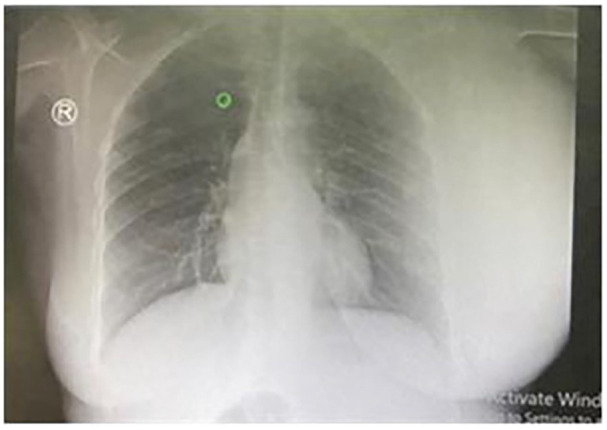

Primary breast lymphoma (PBL) is a rare malignant lymphoid neoplasm limited to the breast, accounting for about 0.15% of all malignant breast tumors and 1.7% to 2.2% of extra-nodal lymphomas. PBL must be distinguished from conventional breast carcinomas due to different therapeutic approaches. A 25-year-old female presented with a left breast mass. Histopathology and immunohistochemical tests confirmed the diagnosis of diffuse large B-cell lymphoma (DLBCL). She had no similar lesions elsewhere in the body. She received 1 cycle of R-CHOP chemotherapy but absconded from the treatment and succumbed afterward while at home. Recent developments in DLBCL treatment have greatly improved patient outcomes by incorporating targeted medicines like rituximab, increased chemotherapy regimens, new drugs, and individualized treatment techniques. PBL appears to have a worse prognosis; thus, delay or abscondment from treatment is of serious concern when it comes to improving the prognosis of patients with PBL.